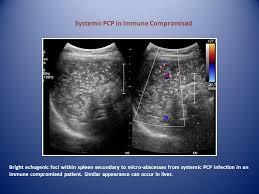

Hepatic PCP

Punctate echogenic foci in liver +/- spleen

After inhaled pentamidine